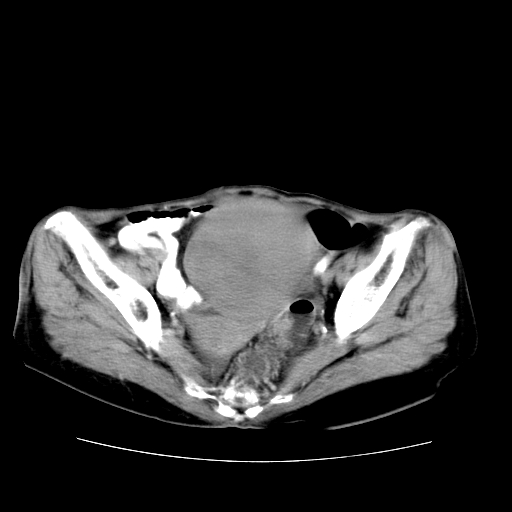

女性,72岁。

主诉下腹部坠痛不适1年余。

子宫增大如孕3月大小,质软,活动可,无压痛。

b超提示:盆腔(子宫前方)低回声团块。

临床诊断:盆腔肿块查。

1、这个肿瘤密度均匀,增强后轻中度均匀性强化,与左侧附件关系密切,肿瘤边缘光整、清晰。

2、左侧卵巢增大呈8×8×10cm大小,实性,表面光滑,边清,左侧输卵管爬行于左卵巢上,子宫萎缩。右输卵管、卵巢萎缩。

3、病理号:092658

左侧卵巢纤维瘤(性索间质肿瘤)

卵巢纤维瘤为良性卵巢性索间质肿瘤,常为单侧发病,当合并腹水或胸腹水时称麦格斯(meigs)综合征,肿瘤切除后胸腹水可消失。ct表现为盆腔内边界清楚的圆形或椭圆形肿块,常有分叶或不规则;肿瘤多为实性,少数为囊性、囊实性,完全囊性者可见壁结节。实性部分与子宫等密度;增强扫描常为轻度强化或几乎不强化。